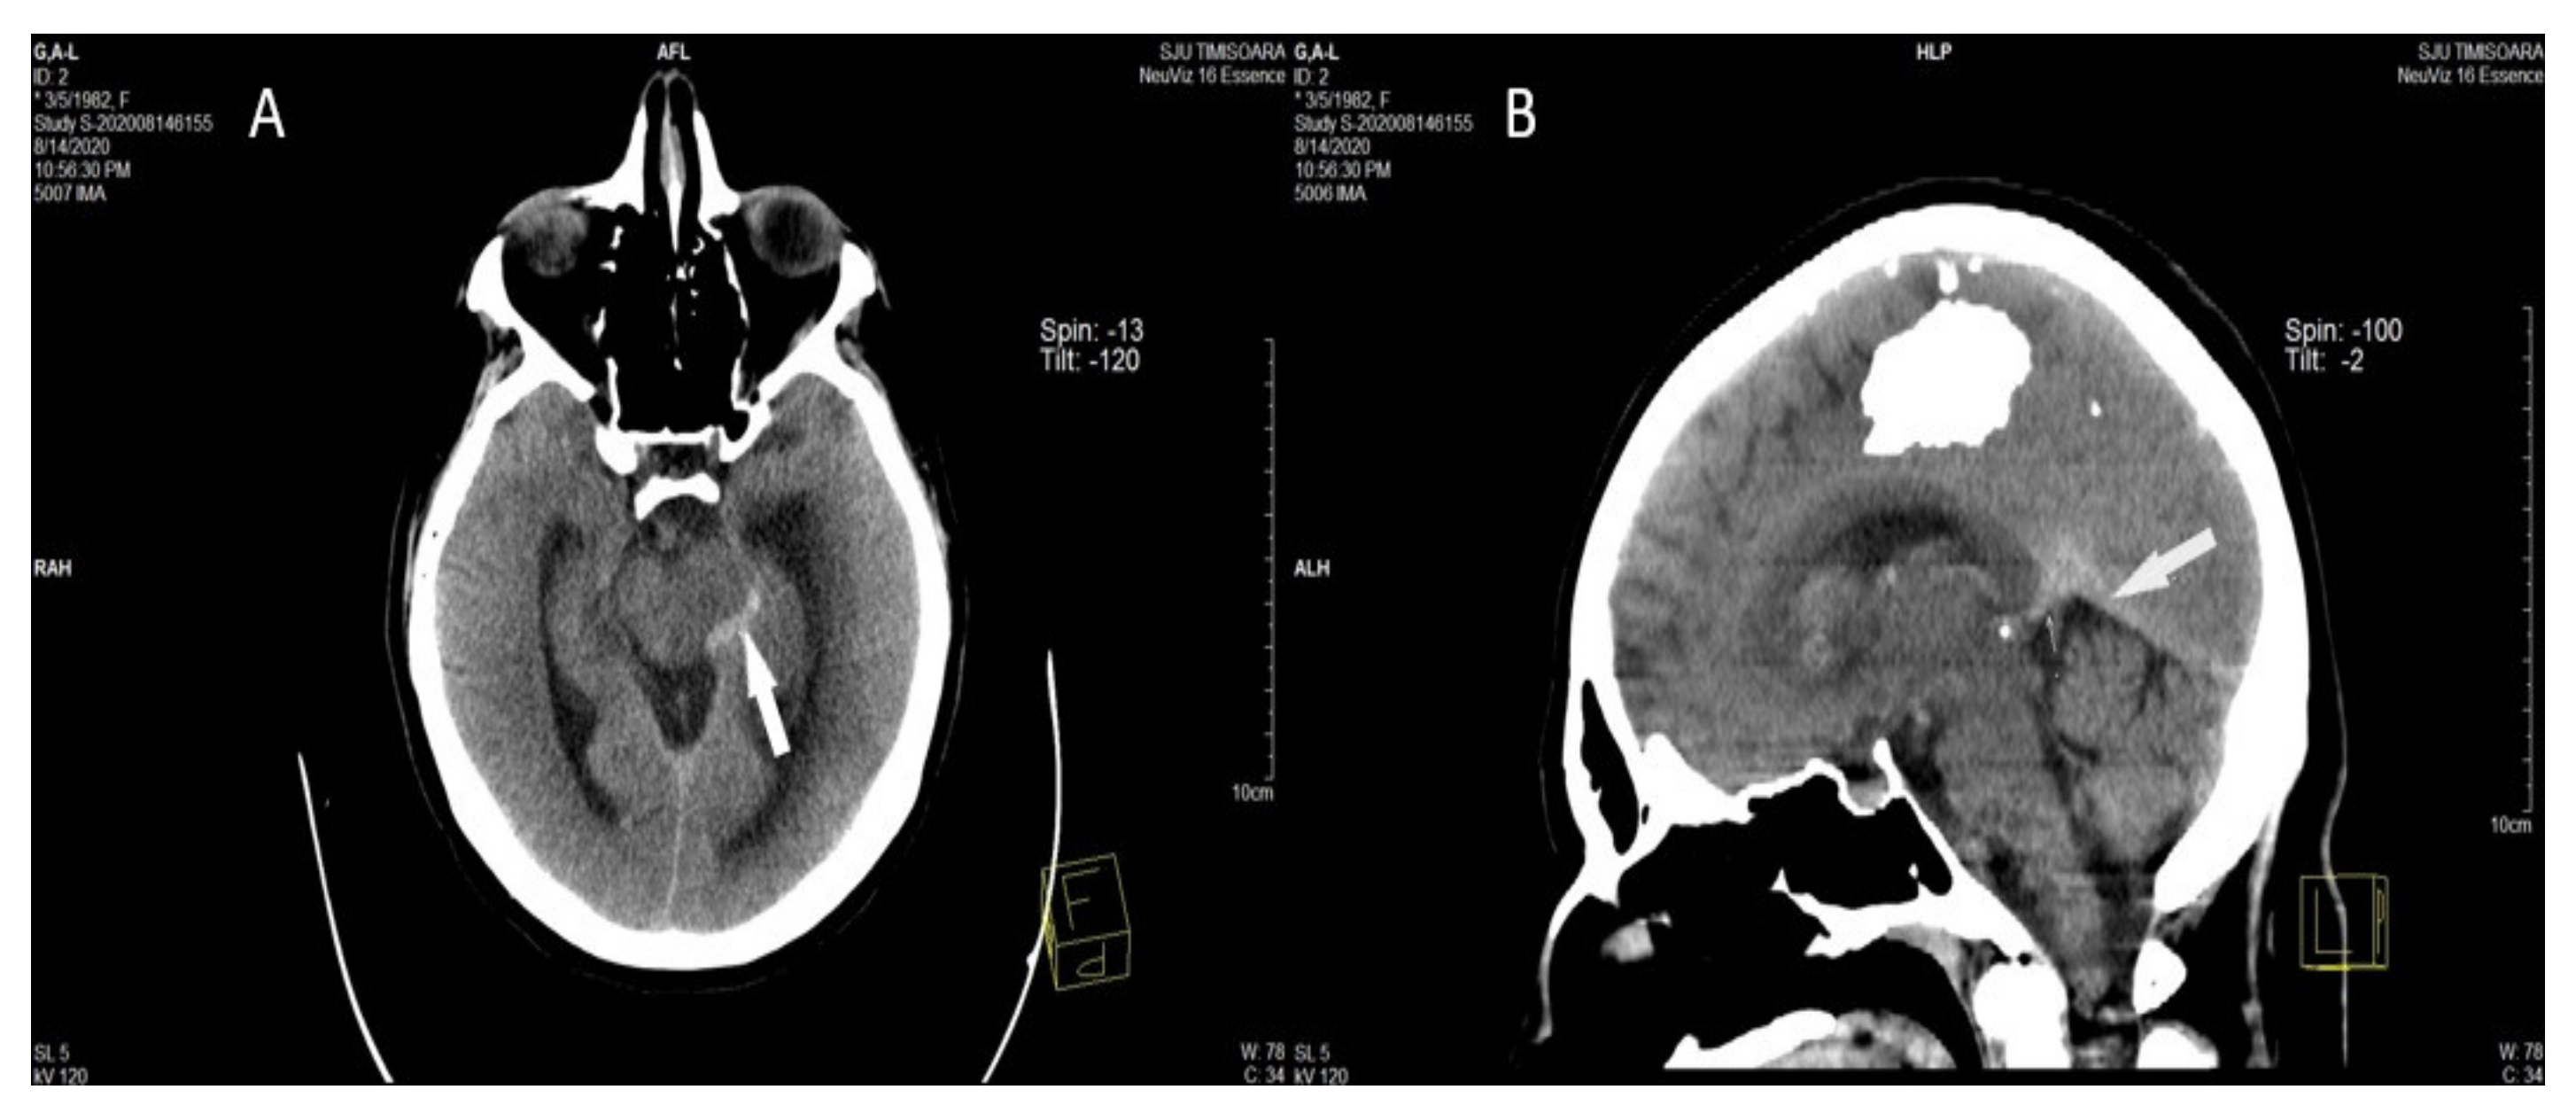

They represent the direct visualization of the venous clot inside the occluded cerebral vein, or dural sinus, and can be observed in about one-third of all CVT patients. They are the “cord sign”, the “dense triangle sign,” and the “empty delta sign” [6,74,79,80]. (Figure 3) [58].

Figure 3.

A, B. Axial (A) and MPR sagittal (B) non-contrast head computed tomography performed in the acute phase shows hyperdense appearance (acute thrombosis) of the left lateral mesencephalic [58].